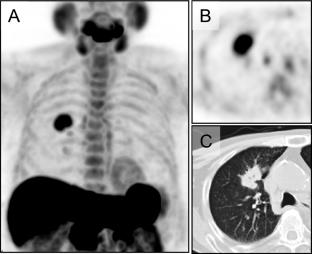

With institutional review board approval, 67 localized NSCLC patients eligible for CIRT between 2007 and 2012 were included. Single-fraction doses of 40–50 Gy were irradiated. MET PET imaging using the Toshiba Aquiduo or Siemens Biograph 16 commenced 20 min post 740 MBq MET injection before CIRT. Experienced radiologists analyzed the images, defining metabolic tumor volume (MTV) as areas with SUV > 1.5. Statistical analysis was performed using SPSS 29, including Cox proportional hazard models for disease-free and overall survival.

Seven cases with Tis of T stage were excluded because of low MET radiotracer uptake. A total of 60 patients were analyzed: 36 males and 24 females with a mean age of 73 years; 35 cases of T1, 24 cases of T2, and one T3 case. The average follow-up period was 74.3 months. The univariate Cox proportional hazard analyses showed that SUVmax, MTV, and total lesion retention (TLR) correlated with disease-free survival (DFS), while no significant difference was noted in treatment dose. For overall survival (OS), solid tumor diameter, SUVmax, MTV, TLR, and sex showed significant correlations in the univariate analysis. The multivariate analysis identified MTV as the only significant prognostic factor for both DFS and OS. Kaplan–Meier survival curves further supported these findings, with log-rank tests indicating a significant difference in survival duration related to MTV in both DFS and OS.